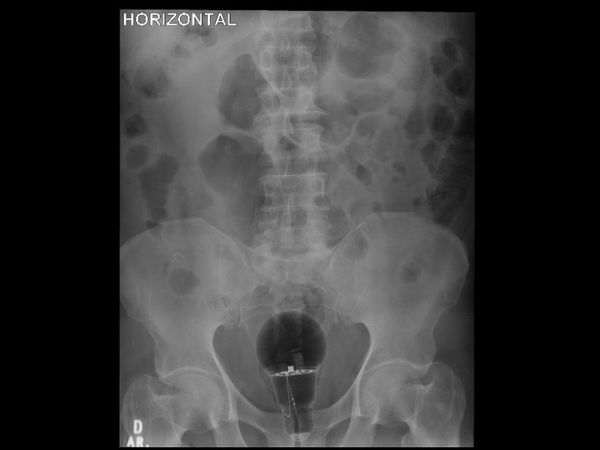

哥伦比亚肠胃病学家兼内科医生朱利安经常在推特分享病例,3月中旬他在推特贴出一张X光照,写道“53岁男性患者,直肠指诊难以触及的体内(未知)异物,该用内视镜移除?”

附图的X光照可以看到,病患骨盆位置附近出现一个大灯泡,甚至可以看到疑似金属电线的构造。

朱利安表示,这名病患可以说非常幸运,因为灯泡没有破裂。